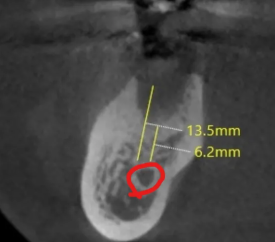

24.06.21 잇몸뼈 회복으로 신경관 상방 치조골 6.2mm 확보

발치 후 회복 기간 동안 정기적으로 체크하며 잇몸뼈의 두께가 확보되는지 확인하였습니다.

약 3개월 정도 기다리는 동안 신경 위로 약 6.2mm의 잇몸뼈가 확보된 것을 확인하고 신경관 임플란트 식립을 진행하였는데요.

저희 의료진과 정기적으로 소통하시며 잘 협조해 주신 환자분 덕분에 13.5mm의 초기 고정력을 얻기 충분한 길이의 임플.란트를 심을 수 있었습니다.